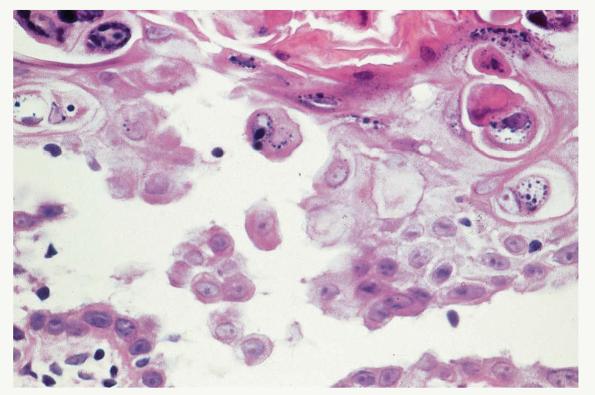

Histopathology. Spongiosis and intraepidermal vesiculation occur in acute lesions . There is a superficial perivascular Iymphohistiocytic infiltrate with exocytosis of lymphocytes into spongiotic zones. The infiltration is usually mild. In acute lesions, the compact, thickened stratum corneum of acral skin remains intact, and the epidermal thickness is normal. With chronicity, spongiosis diminishes; acanthosis and parakeratosis predominate with variable crusting. Difficulty in differential diagnosis with pustular psoriasis may occur because of the formation of vesiculopustules in older lesions. A periodic acid-Schiff (PAS) stain should always be performed on vesicular lesions of the palms and soles, because tinea manus/pedis may mimic dyshidrotic dermatitis histologically. |